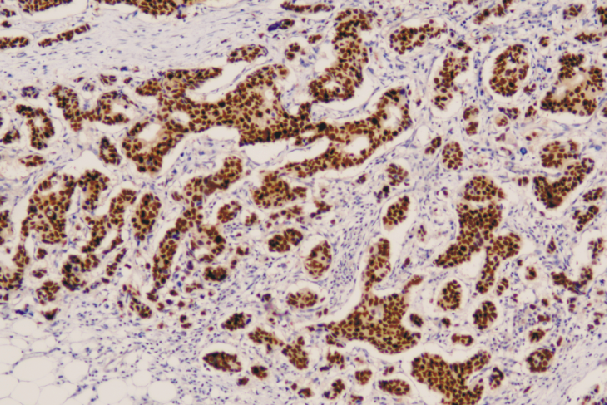

Estrogen Receptor(ER)鼠抗人雌激素受体单克隆抗体

ER受体存在于正常子宫的内膜层、肌层细胞、正常乳腺的上皮细胞和部分(约50-60%乳癌患者)乳腺癌细胞。研究表明,ER阳性的乳癌病人对激素治疗有效,且预后好于ER阴性组。因此,ER、PR和C-erbB- 2共同用于指导患者治疗。

- 阳性部位:胞核

- 适用组织:石蜡切片

- 预处理:热修复